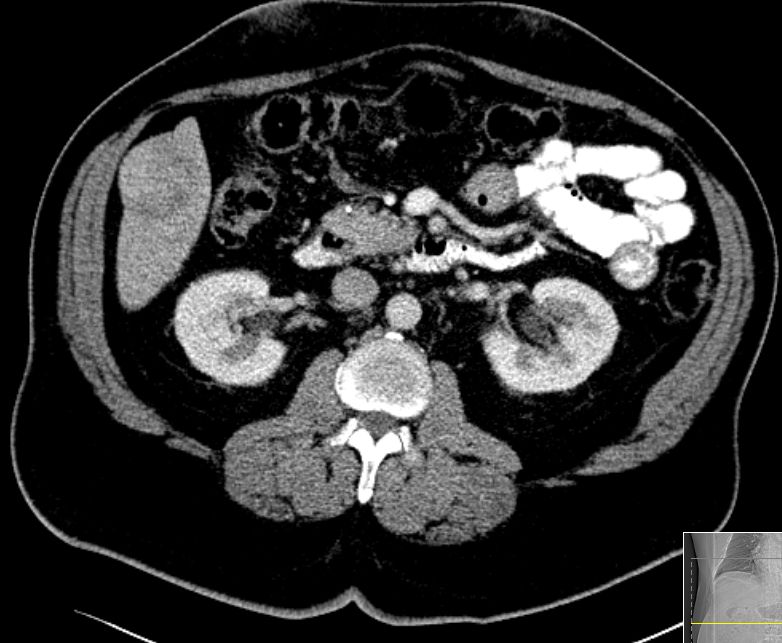

| CT | 79-jähriger Mann mit Raumforderung im rechten Leberlappen. AFP > 3000.![]() | ||